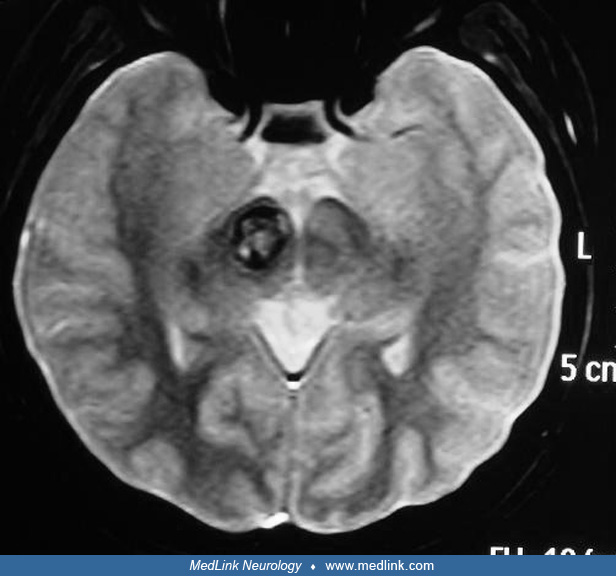

From www.medlink.com

Thalamic hemorrhage MedLink Neurology Thalamic Hemorrhage Location Thalamic hemorrhage can have a highly varied clinical presentation depending on the exact location of the hemorrhage. Intracerebral hemorrhage (ich), a subtype of stroke, is a devastating condition whereby a hematoma is formed within the brain parenchyma with or without blood extension into. Hemorrhagic stroke may be further subdivided into intracerebral hemorrhage (ich). Hemorrhagic strokes, on the other hand, are. Thalamic Hemorrhage Location.

Thalamic hemorrhage MedLink Neurology Thalamic Hemorrhage Location A thalamic stroke is the result of a disruption in blood flow to the thalamic region of the brain. Thalamic hemorrhage can have a highly varied clinical presentation depending on the exact location of the hemorrhage. Hemorrhagic stroke is due to bleeding into the brain by the rupture of a blood vessel. Hemorrhagic strokes, on the other hand, are due. Thalamic Hemorrhage Location.